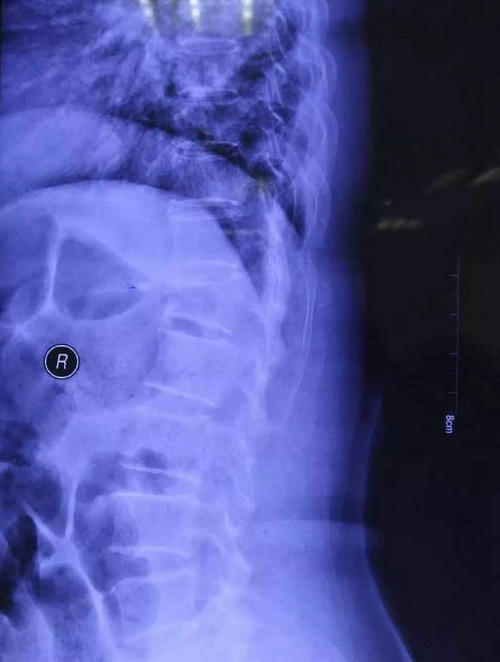

张长江主任指示付卫平,余耀坤两位医师迅速完善相关检查,明确诊断,排除手术禁忌症。各项检查结果都证实了张长江主任的判断——胸12椎体压缩骨折。

▲ 患者术前正侧位影像